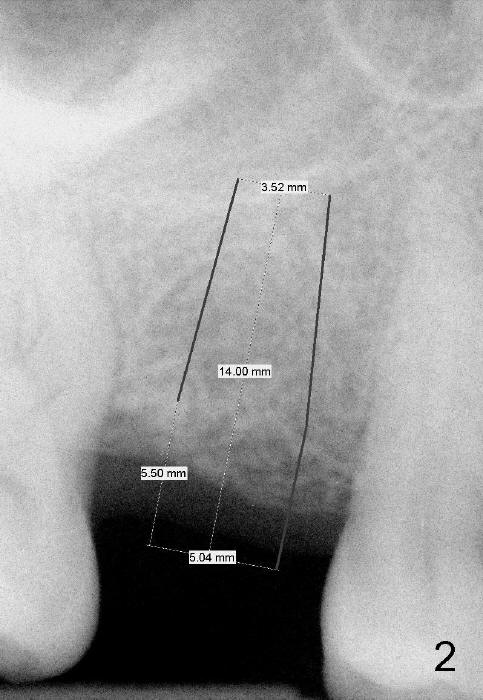

The 42-year-old lady is a dental phobic. The tooth #3 (residual root) is extracted 3.5 years ago. Finally she returns for implant (Fig.1). The mesiodistal space allows to place a 5x14 mm implant (Fig.2). Bone density is felt low when a 1.6 mm pilot drill is used. Bone condensation proceeds with bone expanders 2.6 mm (Fig.3) to 3.8 mm (Fig.4) 12 mm deep. Bone density is felt to increase with each larger expanders. When a 4x11 mm implant is placed (Fig.5), the insertion torque is 15 Ncm. When the diameter and length of the implant increase (Fig.6), the insertion torque is >60 Ncm. To have primary stability, the implant should be two sizes larger than the last expander (compare Fig.4,6)! In addition, the majority portion of the expanders is cylindrical (Fig.3,4), whereas the implant is tapered (Fig.5,6).